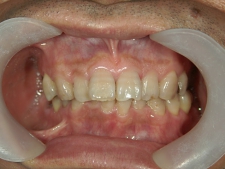

矯正歯科 治療後矯正歯科 全顎ワイヤー矯正 治療後矯正歯科(全顎ワイヤー矯正)治療後

矯正歯科 治療後 左上6番欠損のため、7番を6番の位置へ前方牽引

no.22_8175_治療後_右.jpgno.22_8175_治療後_正面.jpgno.22_8175_治療後_左.jpg